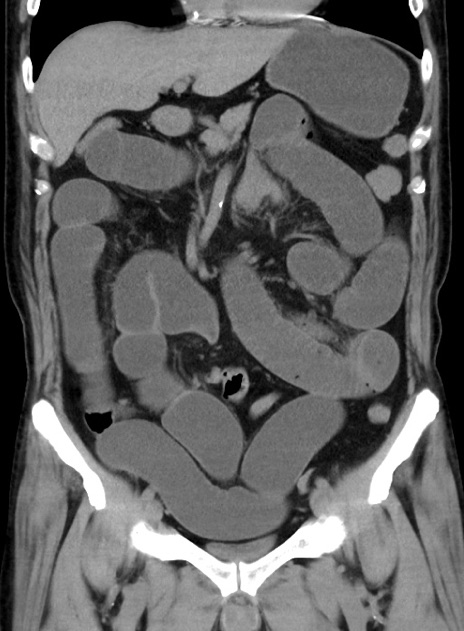

症例38(冠状断像)

【症例】70歳代 男性

【主訴】腹痛・嘔吐

【現病歴】昨晩より、嘔吐・腹痛あり。今朝になっても嘔吐あり。来院。

【既往歴】心臓バイパス手術、開腹胆摘、腸閉塞

【身体所見】BP 107/71mmHg、HR 116/min、腹部:平坦、軟、下腹部に軽度圧痛あり。反跳痛なし。

【データ】WBC 15100、CRP 0.32